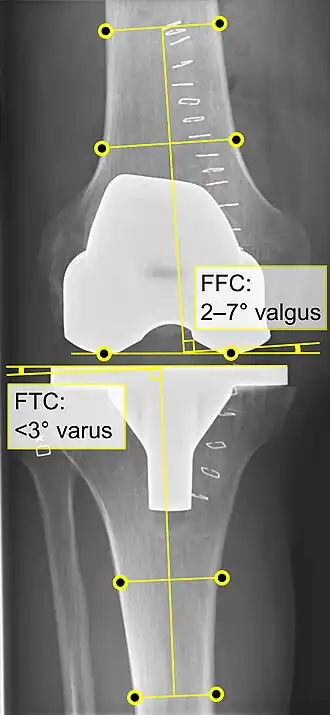

![]() |

Angles commonly measured before knee replacement surgery: |

Knee replacement is routinely evaluated by X-ray, including the following measures:

- FFC: frontal femoral component angle. It is typically regarded as optimal when being 2–7° in valgus.[67]

- FTC: frontal tibial component angle, which is regarded as optimal when being at a right angle. A varus position of more than 3° has generally been found to increase the failure rate of the prosthesis.[67]

- LTC: lateral (or sagittal) tibial component angle, which is ideally positioned so that the tibia is 0–7° flexed compared to at a right angle with the tibial plate.[67]